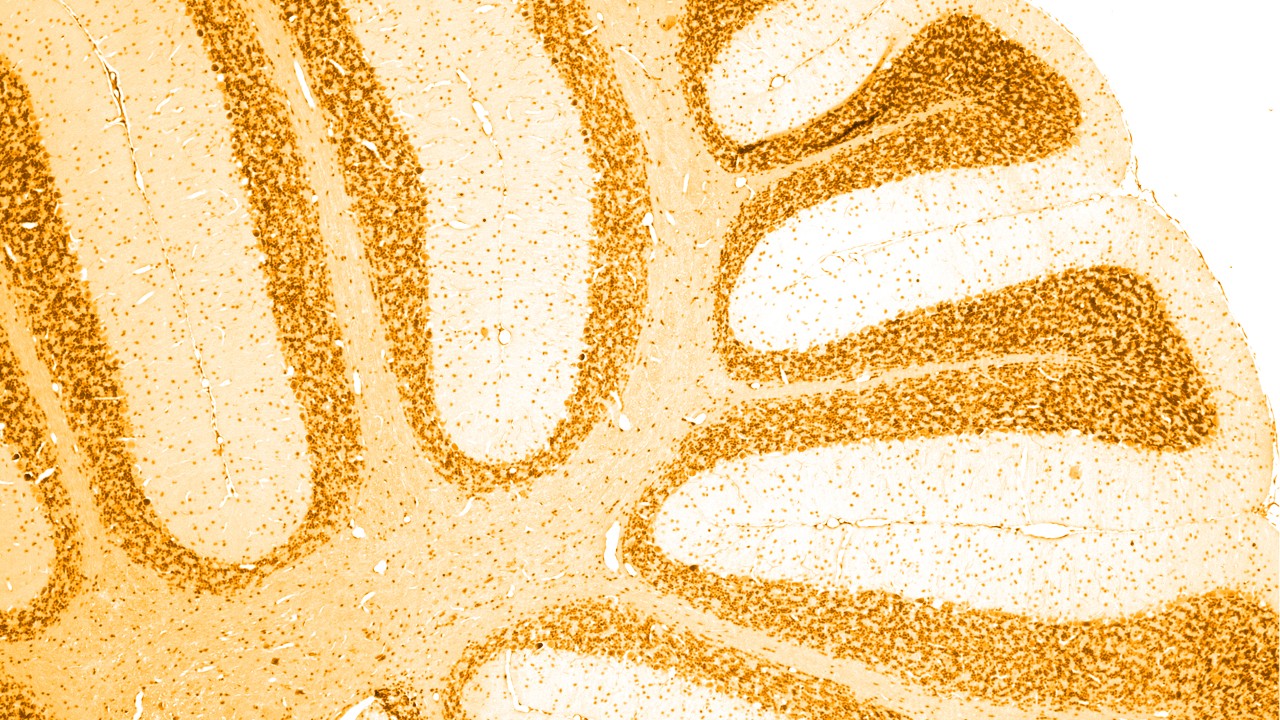

Neurological disorders are diseases of the central and peripheral nervous system. In other words, the brain, spinal cord, nerves and muscles, which regulates and coordinates body activities.

There are a number of different causes of dementia, of which the most common is Alzheimer’s disease, linked with the build-up of abnormal ‘amyloid plaques’ and ‘tau tangles’ in the brain. Certain other types of dementia also have an abnormal build-up of tau protein in the brain; as a group, these are termed ‘tauopathies’.